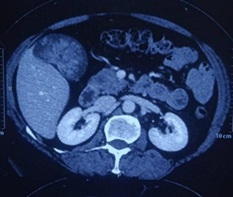

Case Presentation: A 48-year-old female presented with complaints of vague upper abdominal pain for last 10 days.Ultrasound abdomen revealed polypoidal mass filling gall bladder lumen measuring 7x3.8 cm. MRCP revealed hypointense mass lesion within gallbladder lumen with its stalk at the hepatic surface of gall bladder. CT abdomen revealed heterogeneously enhancing gall bladder mass with no regional lymphadenopathy. Serum tumor markers of CEA, CA19.9 were normal. Patient underwent en bloc resection of 2 cm segment IVB liver along with gallbladder. Intraoperative frozen section specimen revealed exophytic polypoidal papillary lesion in distal body of gallbladder measuring 5x4x3 cm. Microscopic features revealed intracholecystic papillary neoplasia with low-grade dysplasia. Regional lymphadenectomy was not performed. Final diagnosis of Intracholecystic papillary neoplasm,gastric type was confirmed and patient was kept on close follow up.